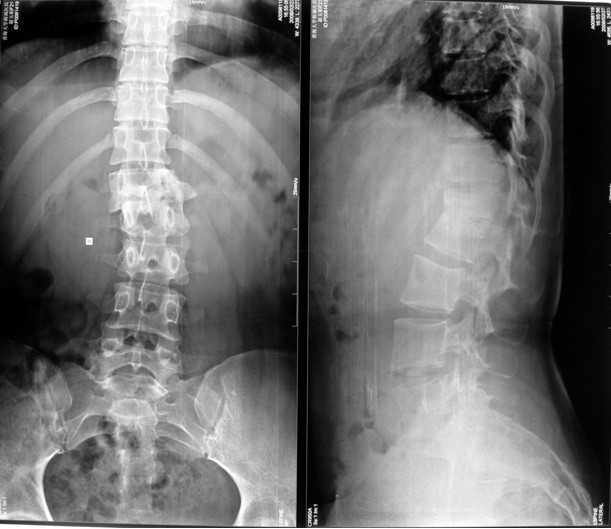

本组46例中男28 例,女18 例。年龄17~67岁,病程6 个月~7年,平均11.3 个月。本组患者均为 L1~S1腰段结核。病灶累及2 个椎体31例(L1-2 6例, L2-3 8例,L3-4 10例,L4-5 5例,L5-S1 2例),3 个或3 个以上椎体15例。合并腰大肌脓肿23列,所有患者均有腰背部疼痛,活动受限,双下肢感觉麻木19例,会阴部感觉减退12例,双下肢肌力减弱12例,腱反射减弱12例,术前后凸角(Cobb 角) <30°者12例, 30°~60°者28 例, >60°者6 例,Cobb角平均32.3°4例患者是二次手术。术前均行X线片、CT或者MRI检查。术后病理检查确诊为脊柱结核。

图11-a术前